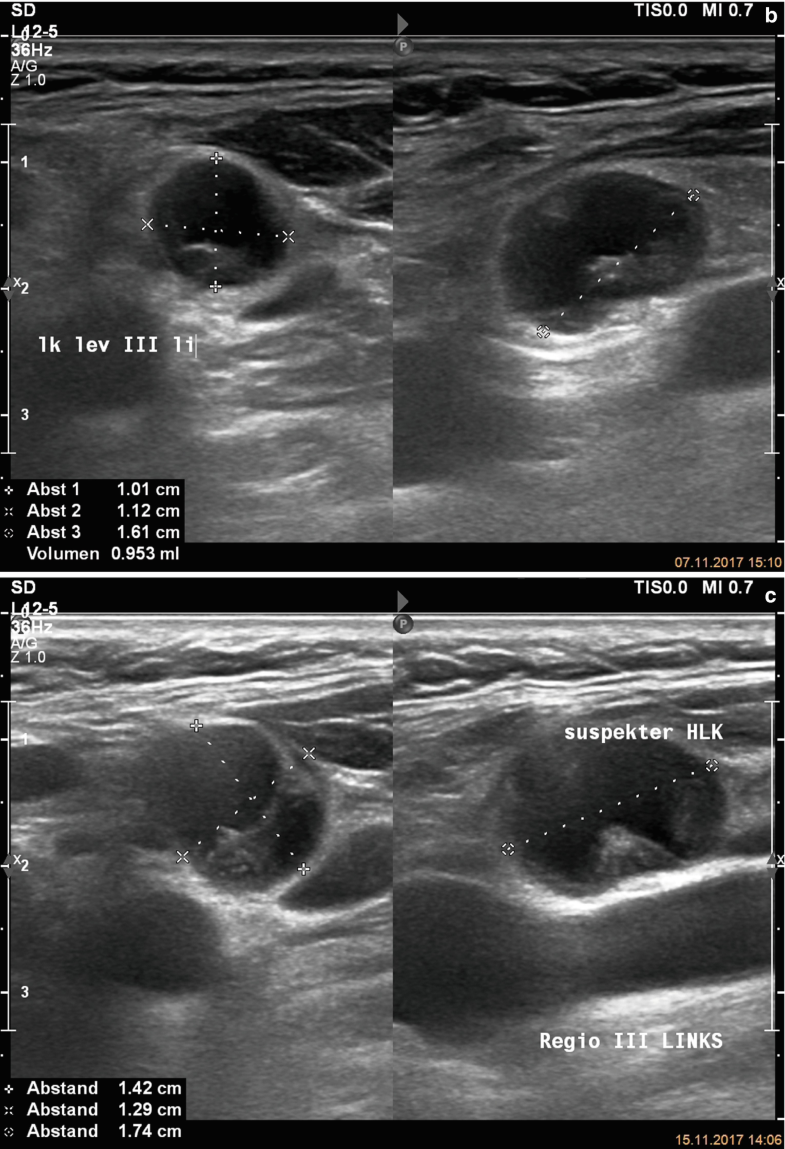

Spread of thyroid cancer to the lymph nodes in the neck is common and increases the risk of cancer recurrence. I had an ultrasound done in 2012 but the report for this scan never reached my previous doctor's practice and so nothing was. Ultrasound uses sound waves to create images of the body on a computer monitor. 8.4, 8.5, 8.6, 8.7, and 8.8). The first lymph node cancer cells spread to is known as the sentinel node.

Colon Cancer Ultrasound Radiology Case Radiopaedia Org from prod-images-static.radiopaedia.org To see whether the cancer has spread, some or all of the lymph nodes are removed and checked for cancerous cells. We prospectively studied 19 patients referred to the institut gustave. It can be used with a fine needle aspiration test or core biopsy test to accurately direct the tip of the needle into the lump. If this lump is of concern then a biopsy would be the next step. They deliver blood from your heart to your brain. Head and neck cancers include cancers in: However, an ultrasound can tell if a lymph node has an abnormal architecture possibly because it is infiltrated by tumor. Sonography, when performed by an experienced examiner, can be used for evaluation of many pathologies in the head and neck area.

An ultrasound of the thyroid produces pictures of the thyroid gland and the adjacent structures in the neck. The scan is painless and only takes a few minutes. It can detect abnormal tissues, growths, and cysts and give a suspicion of cancer based on how those images look. Confirming that a lump in the neck is developing from the thyroid or connected tissue. Doctors and pathologists do not use internal ultrasound scan frequently to detect lymphoma. Ultrasound guidance is used to perform thyroid biopsies and improves the diagnostic accuracy of fine needle biopsy. The first lymph node cancer cells spread to is known as the sentinel node. Ultrasounds can't show lung cancer or bone cancer. Some of the indications for thyroid or neck ultrasound are thyroid nodules, goiter, thyroid cancer and other neck masses. For neck or thyroid mass see ent. To see whether the cancer has spread, some or all of the lymph nodes are removed and checked for cancerous cells. Fna might also be used in patients whose cancer has been treated by surgery and/or radiation therapy , to help find out if a neck mass in the treated area is scar tissue or if it's a return (recurrence) of the cancer. The lymph nodes in the neck are often the first place cancer cells spread to outside the primary site.

Figure 1 From Post Thyroidectomy Neck Ultrasonography In Patients With Thyroid Cancer And A Review Of The Literature Semantic Scholar from d3i71xaburhd42.cloudfront.net I have ocd and my obsession of 30 years is that i have a tumor on in my throat or neck. Additionally, how do they test for thyroid cancer? An ultrasound scan of the neck uses sound waves to build up a picture of your neck and lymph nodes. Ultrasounds can't show lung cancer or bone cancer. The diagnosis of papillary thyroid cancer is made with an ultrasound guided small sampling of cells from the thyroid gland or neck lymph nodes (or both in some instances). Our doctors also use ultrasound to check lymph nodes in the neck, where some forms of thyroid cancer can spread. For most types of cancer, a biopsy is the only sure way for the doctor to know if an area of the body has cancer. We prospectively studied 19 patients referred to the institut gustave.

While it can't diagnose cancer, it can detect the abnormal tissues that may possibly be cancerous. Ultrasound is often one of the first line tests in the detection of cancer. For neck or thyroid mass see ent. Lymph nodes are part of the lymphatic system, which helps to protect us from infection and disease. Some of the indications for thyroid or neck ultrasound are thyroid nodules, goiter, thyroid cancer and other neck masses. Ultrasound imaging is a noninvasive medical test that helps physicians diagnose and treat medical conditions. Part of the throat (cancers of the oropharynx and tonsils, nasopharynx and hypopharynx) the nose or sinuses (nasal and sinus cancer) the salivary glands. Ultrasound guidance is used to perform thyroid biopsies and improves the diagnostic accuracy of fine needle biopsy. Sonography has an accuracy rate of about … Fna might also be used in patients whose cancer has been treated by surgery and/or radiation therapy , to help find out if a neck mass in the treated area is scar tissue or if it's a return (recurrence) of the cancer. If the person has a lump in the neck, an fna can show if the mass is from cancer spread. It can be used with a fine needle aspiration test or core biopsy test to accurately direct the tip of the needle into the lump. It can detect abnormal tissues, growths, and cysts and give a suspicion of cancer based on how those images look.